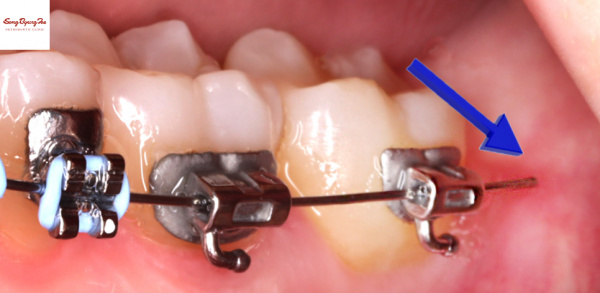

또 다른 경우는 위 그림처럼

철사가 아예 빠져나온 경우입니다.

주로 단단한 음식이나 부피가 큰 음식을 씹은 경우

철사가 이를 버티지 못하고 휘어지게 되면서

브라켓에서 빠져나오는 현상이 나타납니다.